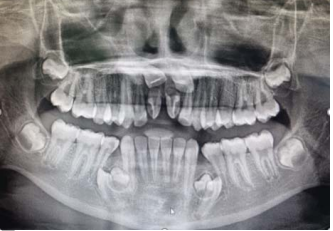

Uma criança de 11 anos de idade, 32 kg, apresenta queixa de demora de erupção dos incisivos permanentes superiores. Observe o aspecto clínico e radiográfico do caso descrito e julgue os itens a seguir.

Apenas em um terço dos casos, dentes supranumerários na dentição decídua são seguidos por um dente supranumerário na dentição permanente.